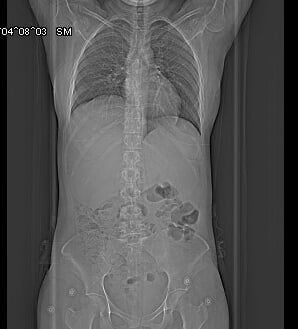

liver canser metastasized from colorectal canser

- My sister has stage 4 colon cancer that has metastasized to her liver and has been undergoing chemotherapy for about 8 sessions. After 3 sessions, the masses in her liver shrank, but later, according to the CT scan results, the volume of the masses in her liver has not decreased any more, and the chemotherapy has caused severe physical weakness. Do you think it would be better if she stopped chemotherapy?